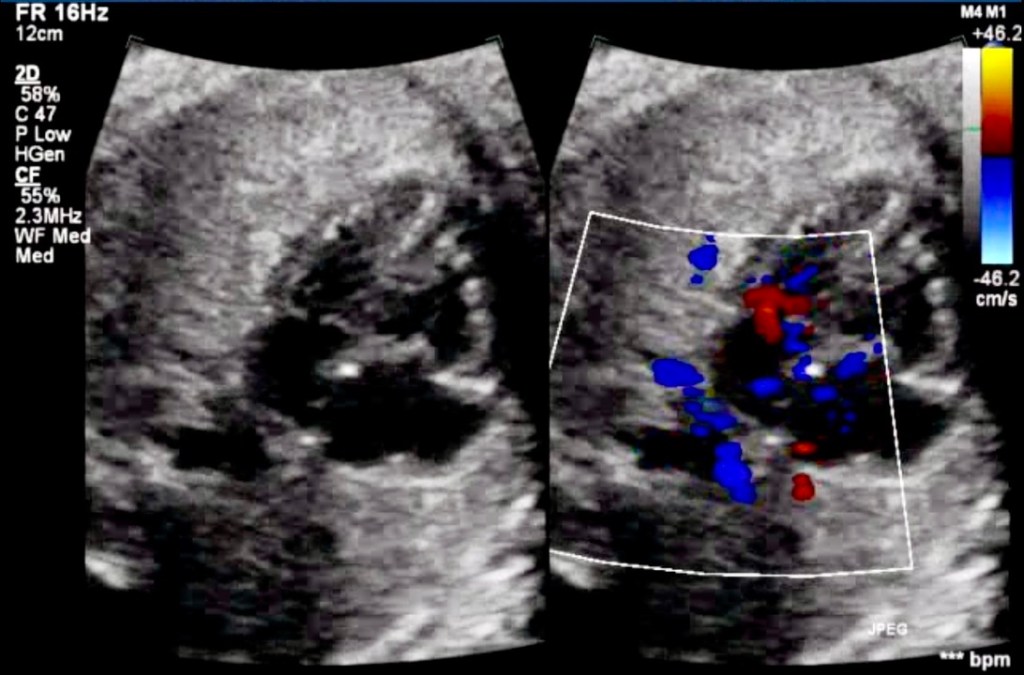

Three-Vessel View (3VV)

Smooth Posterior Wall of LA

- The posterior wall of the LA typically appears irregular due to pulmonary vein entry points. A smooth posterior wall raises suspicion.

- Initial Screening Views: Use the 4-chamber to track drainage of pulmonary veins, 3VV, and 3VT views.